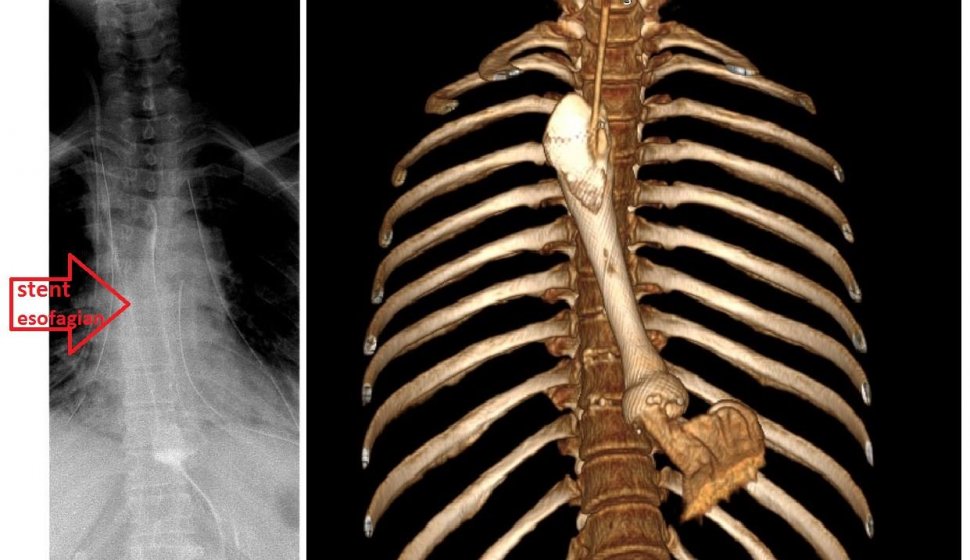

"În urmă cu mulți ani, pacienta a înghițit sodă caustică, motiv pentru care la acea vreme i s-a făcut o gastrectomie (i-a fost scos stomacul). În tratamentul stenozei esofagiene restante s-a simțit nevoia unei dilatații esofagiene, pentru că un țesut stenozat post ingestie sodă caustică nu mai este elastic ca un țesut normal. Una dintre complicațiile manevrelor de dilatație este ruptura esofagiană, ceea ce s-a produs și în acest caz. Doctorul care a monitorizat și tratat pacienta a constatat imediat ruptura esofagiană și a pus un stent acoperit în urgență. Acesta este ca o mică "conductă" care, în situația dată, avea scopul să acopere pe dinăuntru esofagul și să astupe acea fisură”, explică dr. Florin Chirculescu, medic primar Chirurgie Toracică, doctor în Științe medicale și coordonatorul secției de Chirurgie Toracică din cadrul SUUB.

Ruptură esofagiană poate duce la mediastinită. Aceasta este o inflamație urmată de infecție a țesuturilor din mediastin, care are o mortalitate extrem de ridicată, de aproximativ 50%.

Echipă multidisciplinară de la Spitalul Universitar de Urgență din București care a preluat cazul a îngrijit pacienta chirurgical, medical și în Terapie Intensivă. "Am preluat pacienta și am operat-o, în sensul că am făcut mediastinotomiile, am deschis mediastinul pe ambele părți pentru evacuarea țesuturilor necrotice, a secrețiilor care se adunaseră în mediastin", mai spune dr. Chirculescu.

Stentul pus pe esofag îi permite pacientei să se hrănească natural, precoce și singură, ceea ce este un mare avantaj față de a fi hrănită prin jejunostomă, care presupune o gaură în jejun (intestinul subțire) prin care se introduce mâncare specială semilichidă. În plus, pacienta are șanse mari să rămână cu esofagul ei și acea fistulă să se închidă, iar astfel ea să revină la viața pe care o avea.